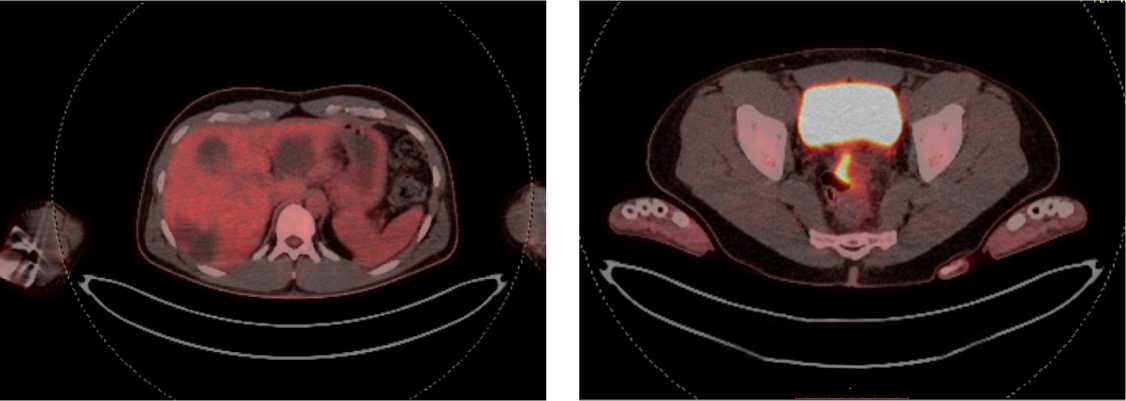

С целью оценки метаболической активности метастазов и первичной опухоли пациенту выполнено ПЭТ/КТ всего тела с 18-ФДГ: патологическая активность стенки среднеампулярного отдела прямой кишки 38,4 × 13,3 мм, SUV max 13,50 (рис. 13).

Рис. 13. Результаты позитронно-эмиссионной томографии с 18-ФДГ на фоне иммунотерапии пембролизумабом у пациента 38 лет с диагнозом метастатический колоректальный рак с признаками микросателлитной нестабильности; патологическая активность стенки среднеампулярного отдела прямой кишки 38,4 × 13,3 мм, SUV max 13,50 (март 2024 г.)

Fig. 13. Results of positron emission tomography with 18-FDG during immunotherapy with pembrolizumab in a 38-year-old patient diagnosed with metastatic MSI-H colorectal cancer; pathological activity of the wall of the mid-ampullary part of the rectum 38.4 × 13.3 mm, SUV max 13.50 (March 2024)